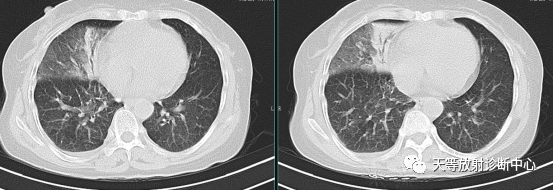

▲BALT,肺炎型,实变影中见支气管充气征

病例来源:李梦杰 刘鹏发表于《临床肺科杂志》2019年12月《气管黏膜相关淋巴组织结外边缘区 B 细胞淋巴瘤 1 例报告》

上图:肺结核,肺内呈大片状实变影,支气管充气征及支气管播散,沿支气管束呈爬行分布。

▲胞内分枝杆菌肺病,右肺中叶支气管扩张,右肺下叶小叶中心结节